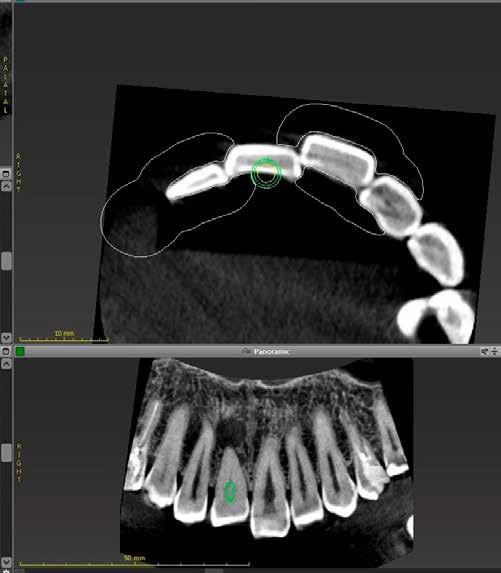

A radiológiai felvételek elemzése során a fog gyökércsúcsának megfelelően radiolucens elváltozást észleltünk, valamint a fognyak területének megfelelően szintén egy radiolucens területet figyelhettünk meg (1–2. ábra). Az elváltozások kiterjedésének és mélységének pontosabb meghatározása érdekében CBCT-felvétel készült (3. ábra). A felvétel alapján Heithersay-féle III. osztályú külső fognyaki gyökérfelszívódást diagnosztizáltunk (Heithersay Class III external cervical invasive root resorption; ECIR). Ezzel egyidejűleg pedig szimptomatikus periapikális periodontitis is fennállt. Ezt követően a pácienst a vizsgálati eredményekről, a kezelési alternatívákról és a várható prognózisról is tájékoztattuk.

A CBCT-felvételek rendkívül hasznos információkkal szolgálhatnak az endodonciai kezelések során. A felvételek segítségével meghatározhatjuk a külső fognyaki rezorptív lézió kiterjedését, felismerhetjük és osztályba sorolhatjuk az esetleges periapikális elváltozásokat, valamint nagyobb pontossággal felmérhetjük a fog belső anatómiai felépítését. Több szerző egymástól függetlenül is igazolta, hogy a CBCT rendkívül hasznos eszköz a rezorptív léziók diagnosztizálása során.

3. a–d ábra: A koronális síkú metszeten jól megfigyelhető a lézió mesio-distalis kiterjedése (a), a szaggitális síkú metszet a lézió vesztibulo-orális nagyságát mutatja (b), a gyökércsúcs körül elhelyezkedő lézió a 3 dimenziós rekonstrukciós képen és a mesio-disztális irányú metszeten is jól megfigyelhető (c–d).

A cikkekben bemutatott esetnél a kezelésre szoruló fog gyökércsúcsánál periapikális lézió volt megfigyelhető és ezzel egyidejűleg külső fognyaki gyökérrezorpció is fennállt. A periapikális és a rezorptív lézió méretének pontos meghatározását és térbeli elhelyezkedésének vizsgálatát CBCT-felvétel segítségével végeztük.